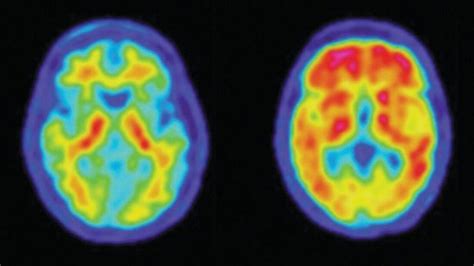

Now, you might be wondering, “Why is looking at function so important?” Great question, guys! The real power of PET scans lies in their ability to detect diseases at their earliest stages and to provide crucial information for treatment planning and monitoring. For instance, in oncology (cancer care), PET scans are a game-changer. They can help doctors differentiate between cancerous and non-cancerous tumors, detect if cancer has spread to other parts of the body (metastasis), and assess how well a tumor is responding to treatment. Imagine a patient undergoing chemotherapy. A PET scan can show if the cancer is shrinking or becoming less active before structural changes are visible on other imaging tests. This allows for timely adjustments to the treatment plan if it’s not working effectively. Beyond cancer, PET scans are invaluable for diagnosing and managing neurological disorders. They can help identify changes in brain activity associated with Alzheimer’s disease, Parkinson’s disease, epilepsy, and other brain conditions. For example, in Alzheimer’s, PET scans can reveal patterns of reduced metabolic activity in specific brain regions, offering a clearer picture of the disease’s progression. They’re also used in cardiology to assess blood flow to the heart muscle, helping to diagnose coronary artery disease and determine the extent of damage after a heart attack. In essence, PET scans provide a unique window into the body’s internal processes, offering insights that other imaging techniques simply can’t. This detailed functional information empowers healthcare professionals to make more accurate diagnoses, personalize treatments, and ultimately improve patient outcomes. It’s this ability to see the unseen, the subtle changes happening at a cellular level, that makes PET scans an indispensable tool in modern medicine. They are truly at the forefront of diagnostic imaging, pushing the boundaries of what we can see and understand about human health.